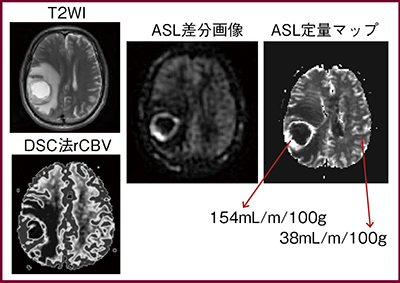

一方,血流が増加する脳腫瘍の場合は,DSC法のTmaxよりもCBFやCBVとの相関が高くなっている(図5)。ASL法では通過時間の影響が包括され,病態によって信号変化があるため,DSC法でTmaxが変化する場合は虚血型,rCBVが変化する場合は新生血管型となる。ASL法で両者を区別するには,transit timeのような新しいパラメータを測定する必要があると考える。また,ASL法の血管信号は塞栓部位を示唆することが多く,臨床的有用性が認められる。

図5 脳腫瘍におけるASL法とDSC法の比較